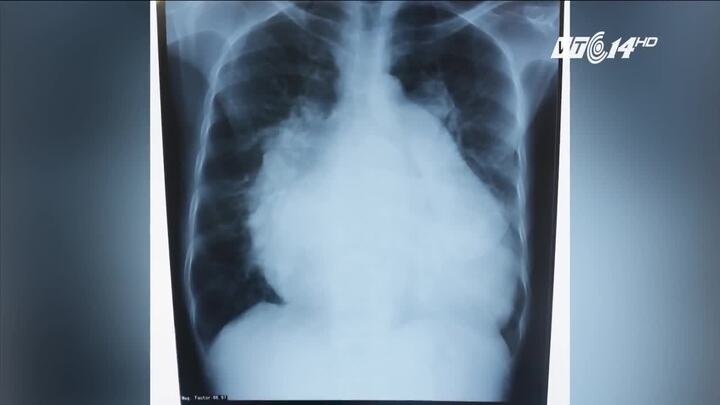

Có tim phình to gấp đôi người bình thường, một phụ nữ 49 tuổi ở Bình Định phải ngủ ngồi suốt 3 năm.